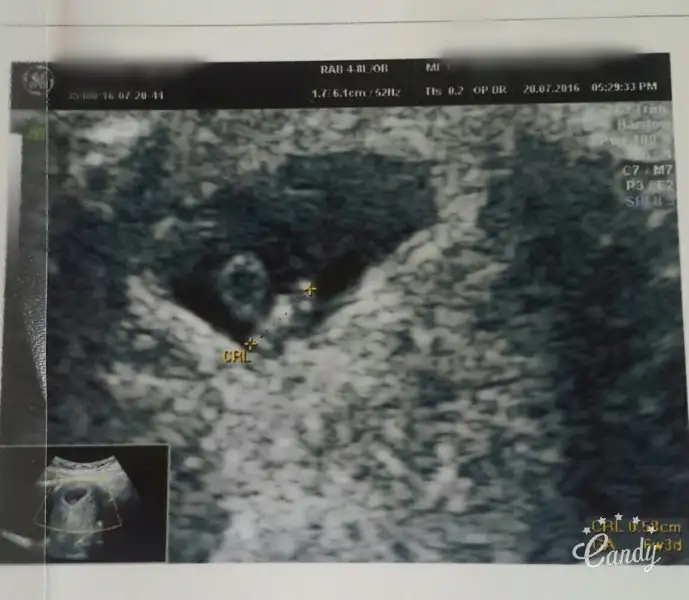

Kiz keseye gore..7+6 yorumlarmisiniz karindan USG fotomuz

Teşekür ederim canım ..Keseye gore erkek canim..